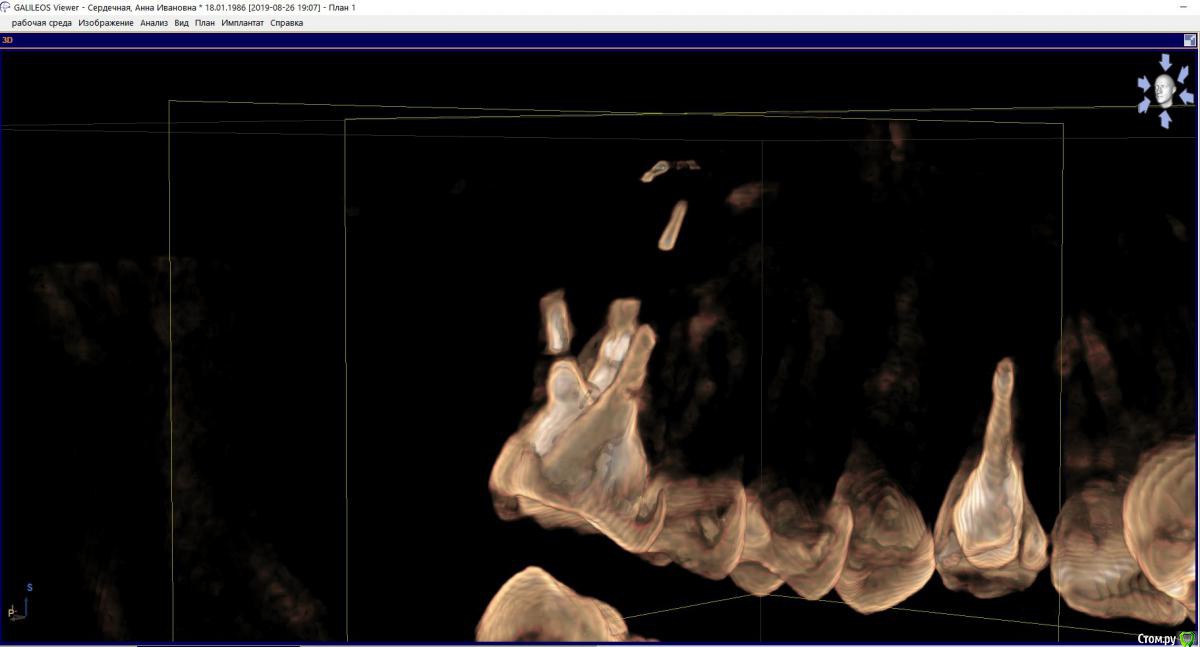

hichin Опубликовано 27 августа, 2019 Поделиться Опубликовано 27 августа, 2019 Здравствуйте, уважаемые стоматологи! Проблемный многострадальный зуб-моляр (26): Дважды попытки удаления кисты левой г/п, вторая попытка удачная, а также гайморотомия и септопластика.Неудачное эндодонтическое лечение, далее повторная попытка перелечивания (смена паст, симптоматика не уходила), которая закончилась сменой стоматолога и лечением с микроскопом. После пломбировки каналов снизилась симптоматика, но пазуха все равно реагировала небольшим утолщением слизистой + любая простуда давала сильную боль на пазуху + зуб. Врачи клиники советовали сделать резекцию. Лоры говорили, что проблема не с их стороны. В члх сделали резекцию с обратной пломбировкой.P.s. так долго эпопея с зубом длится, т.к. все специалисты в один голос говорили о том, что удаление зуба и последующая установка имплантата не факт, что избавит от проблем и будет вообще возможна.Симптоматика c резекцией не ушла.Срезы из свежего КТ прикрепляю. Если можно, прокомментируйте, пожалуйста, срезы. Ссылка на комментарий

колесников Опубликовано 27 августа, 2019 Поделиться Опубликовано 27 августа, 2019 Здравствуйте! По этим срезам изменения а пазухе не значительные,в пределах нормы,характерные для хронического процесса,наличие или отсутствие моляра на него никак не скажется,это самостоятельное заболевание. Над моляром достаточно по..работали,в перспективе он удаляется и замещается на имплант 1 Ссылка на комментарий

hichin Опубликовано 28 августа, 2019 Автор Поделиться Опубликовано 28 августа, 2019 Здравствуйте! По этим срезам изменения а пазухе не значительные,в пределах нормы,характерные для хронического процесса,наличие или отсутствие моляра на него никак не скажется,это самостоятельное заболевание. Над моляром достаточно по..работали,в перспективе он удаляется и замещается на имплант Благодарю вас за ответ.А как быть с оставшимся фрагментом небного корня (если я правильно понимаю, врач удалил не верхушку корня, а как бы середину корня). Реально ли его извлечь и как (через лунку удаленного зуба, через пазуху, тем же путем, что не дошел врач члх)? Основная симптоматика как раз с небной стороны у меня. Ссылка на комментарий

колесников Опубликовано 28 августа, 2019 Поделиться Опубликовано 28 августа, 2019 Или небным доступом или через лунку 1 Ссылка на комментарий